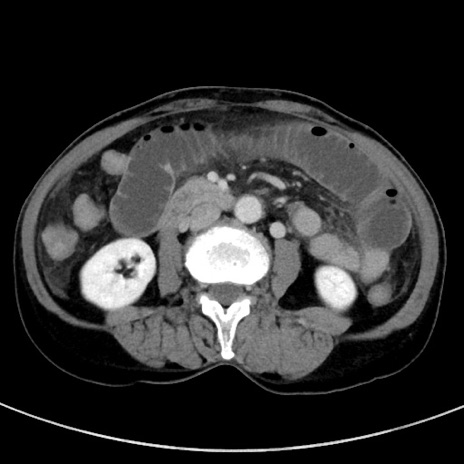

冠状断像

症例23(横断像)

【症例】70歳代女性

【主訴】下腹部痛・嘔吐

【現病歴】2日前より腹痛あり。昨日嘔吐あり。症状改善しないため来院。

【既往歴】胃GISTに対して胃部分切除後。

【身体所見】BT 37.1℃、BP 128/77mmHg、腹部:平坦・軟、下腹部に圧痛あり。

【データ】WBC 10200、CRP 0.31